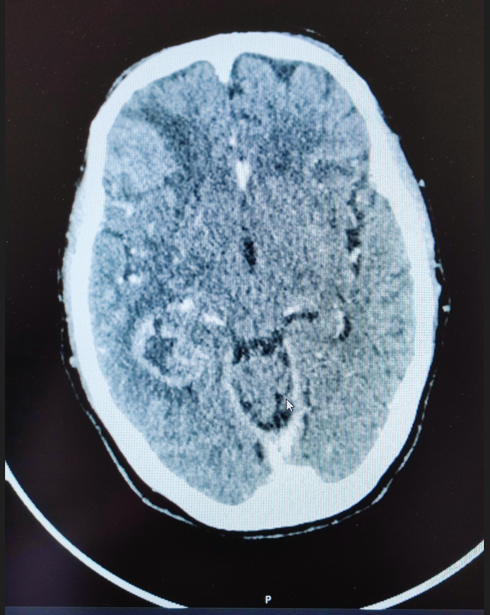

Cranioencephalic computed tomography revealed an expansile cortico-subcortical lesion predominantly centered in the right medial temporal lobe, with significant extension into the adjacent parietal and frontal lobes. The lesion demonstrated heterogeneous contrast enhancement and was surrounded by notable perilesional edema, contributing to local mass effect (Figure 1). A lumbar puncture was performed to analyze cerebrospinal fluid, effectively excluding infectious or lymphoproliferative causes.

Figure 1 Expansile temporal lesion with edema.